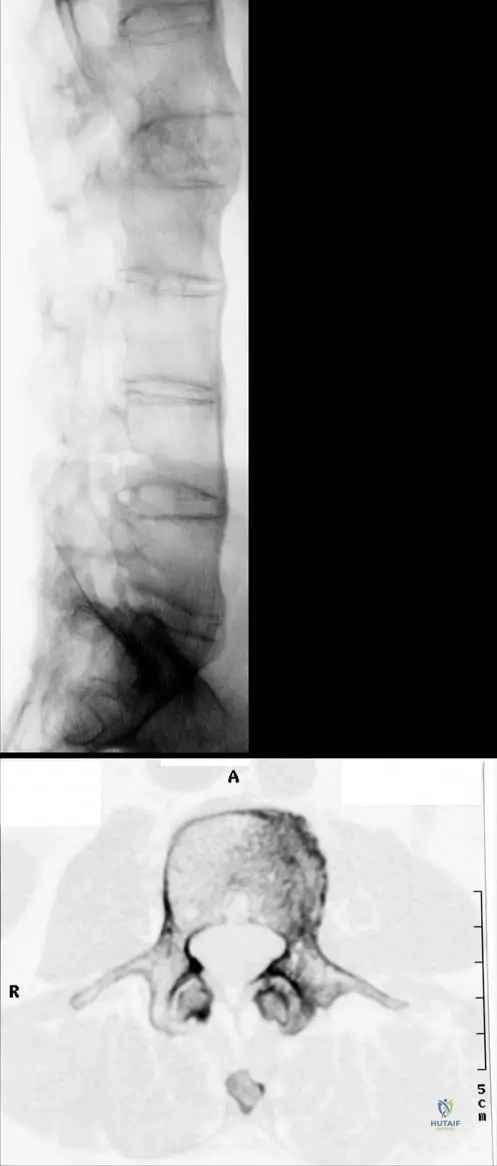

A 40-year-old male with long-standing Ankylosing Spondylitis presents with increasing spinal stiffness. A thoracic spine radiograph is obtained.

Rationale: The clinical context for Fig. 3.34b explicitly describes the image as showing "Typical “bamboo” appearance of the thoracic vertebral column." This appearance is due to the widespread syndesmophyte formation and fusion of the vertebral bodies. Romanus lesion (A) refers to erosions at the vertebral body corners, which are early changes, not the overall fused appearance. Andersson lesion (B) refers to inflammatory lesions in the vertebral bodies or discs. Dagger sign and Trolley track sign are also radiographic findings in AS but describe different aspects (ossification of supraspinous/interspinous ligaments and facet joint fusion, respectively) and are not the specific term used for the overall appearance of the thoracic column in the text.

A 50-year-old male with advanced Ankylosing Spondylitis undergoes a CT scan of his lumbar spine due to increasing rigidity.

Rationale: The clinical context for Fig. 3.35a describes "Typical marginal syndesmophytes." The context for Fig. 3.34c further clarifies that "Reconstruction CT picture reveals erosions of the end-plates of the vertebral bodies and marginal syndesmophytes." Syndesmophytes are characteristic bony outgrowths that bridge vertebral bodies, leading to spinal fusion. They are distinct from osteophytes (A), which are degenerative. While they involve ligamentous ossification, "bony outgrowths from the vertebral body corners" (C) is the most accurate description of their appearance and consequence. Enthesitis (E) is the inflammation at ligament/tendon insertions, which can lead to syndesmophytes, but the syndesmophyte itself is the bony outgrowth.

A 60-year-old male with a long history of poorly managed Ankylosing Spondylitis presents with severe functional limitations.

A 55-year-old male with advanced Ankylosing Spondylitis undergoes a CT scan of his lumbar spine due to severe stiffness. The CT scan reveals bony union of the lumbar facet joints. What is the significance of this finding in AS?

Rationale: Fig. 3.35b shows a "CT scan of the lumbar spine: Bony union of the lumbar facet joints." This bony fusion of the facet joints is a characteristic pathological feature of advanced Ankylosing Spondylitis, contributing significantly to the severe spinal stiffness and immobility seen in the disease. It is not a normal age-related change, a sign of infection, or a rare finding, but rather a direct consequence of the inflammatory process.

A 48-year-old male with long-standing Ankylosing Spondylitis experiences increasing difficulty with deep breathing. A CT scan of his thoracic spine is performed, revealing bony fusion of the costovertebral joints. What is the clinical implication of this specific finding?

Rationale: Fig. 3.34d shows a "CT scan of a thoracic vertebra with bony fusion of the costovertebral joint." The costovertebral joints connect the ribs to the thoracic vertebrae, and their fusion directly restricts rib movement, thereby contributing to the decreased chest expansion, which is a hallmark clinical symptom and diagnostic criterion of AS. It is not directly related to neuropathy, hip pain, or spinal fracture risk, and it is certainly not asymptomatic in terms of respiratory mechanics.